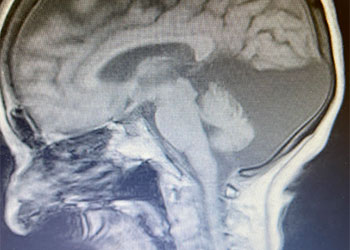

Brain:

Neurosurgeons Collaborate to Treat Giant Symptomatic Meningioma

Hydrocephalus and Brainstem Tumor

Cerebellar Hemangioblastoma